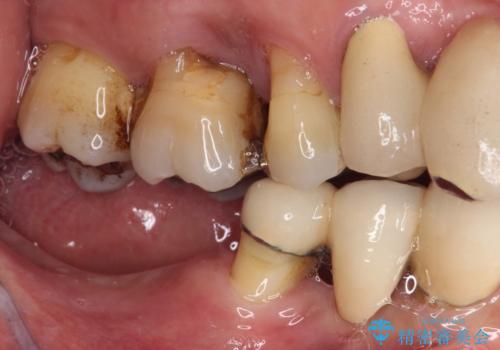

- 以前入れ歯を製作したものの、装着感が悪く使用できなかったとのことで来院された患者様です。

より適合の良い義歯とするため、セラミッククラウンなどは義歯の設計に合わせた土台の歯となるよう全て再製作をし、安定感に優れた義歯を製作することができました。